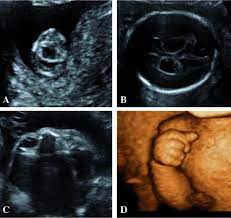

Trisomy 13 is often picked up at 12 weeks with an increased nt. Nosis of trisomy 18 to be made at the time of ultrasound examination. This is referred to as complete trisomy 13 or full trisomy 13. Overlap and difference in ultrasound findings trisomy 13 and trisomy 18. The amniocentesis came back positive for trisomy 13 (preliminary workup showed the abnormality in 97.5% of her cells). This is because each a. The most common abnormalities visualized are cardiac abnormalities, holoprosencephaly, omphalocele, and cleft lip/palate. Diagnosis of trisomy 13 on cvs should be followed up with amniocentesis and serial detailed ultrasound.

Now, this doesn't mean that the abnormalities aren't there. Trisomy 13 is typically due to having three full copies of chromosome 13 in each cell in the body, instead of the usual two copies. Patau syndrome (also known as trisomy 13) is considered the 3 rd commonest autosomal trisomy. Trisomy 13 and 18 are very different in terms of what you can see on ultrasound. Trisomy 13 represents the presence of an extra chromosome 13 resulting from a free copy or translocation. When an afp test indicates a high risk for trisomy 13, usually a level 2 ultrasound (also called a targeted ultrasound) is scheduled. The screening also determines risk of patau (trisomy 13) and edwards (trisomy 18) syndromes, rare and often fatal chromosomal abnormalities. If a maternal fetal dna test result comes back as high risk for a chromosomal abnormality, the recommendation (1) is to confirm the. Greater than 90% of fetuses with trisomy 13 have findings detected on prenatal ultrasound. Targeted sonography identified abnormal fetal anatomy or abnormal biometric measurements in 95% of fetuses with trisomy 13 in the second trimester after 17 weeks' gestation. Smith et al (1999) summarized the findings of 11 cases of trisomy 13 detected on cvs, of which, three cases had confirmed trisomy 13 mosaicism in the fetus. The purpose of this chapter is to focus on the evaluation and management of isolated ultrasound soft markers diagnosed in the second trimester. Fetal ultrasound during pregnancy can also give information about the possibility of trisomy 18 or 13, but ultrasound is not 100 percent accurate because some babies with trisomy 18 and 13 may look the same on ultrasound as those without the syndrome.

Patau syndrome (also known as trisomy 13) is considered the 3 rd commonest autosomal trisomy. Nosis of trisomy 18 to be made at the time of ultrasound examination. Patau syndrome along with down syndrome (trisomy 21) and edward syndrome (trisomy 18) are the only three trisomies to be compatible with extrauterine life. Smith et al (1999) summarized the findings of 11 cases of trisomy 13 detected on cvs, of which, three cases had confirmed trisomy 13 mosaicism in the fetus. Targeted sonography identified abnormal fetal anatomy or abnormal biometric measurements in 95% of fetuses with trisomy 13 in the second trimester after 17 weeks' gestation. Targeted sonography identified abnormal fetal anatomy or abnormal biometric measurements in 95% of fetuses with trisomy 13 in the second trimester after 17 weeks' gestation. How is trisomy 13 diagnosed? But ultrasound is not 100% accurate.

Identify major defects on the sonogram associated with trisomy 13. Fetal ultrasound during pregnancy can also show the possibility of trisomy 13 or 18. When ultrasound findings are consistent with trisomy 13, prenatal karyotyping should be undertaken. Greater than 90% of fetuses with trisomy 13 have findings detected on prenatal ultrasound. This is referred to as complete trisomy 13 or full trisomy 13. After completing this course, the participant should be able: Fetal ultrasound during pregnancy can also give information about the possibility of trisomy 18 or 13. But ultrasound is not 100% accurate. Fetal ultrasound during pregnancy can also give information about the possibility of trisomy 18 or 13, but ultrasound is not 100 percent accurate because some babies with trisomy 18 and 13 may look the same on ultrasound as those without the syndrome. The nt ultrasound is done between 11 and 13 weeks, when baby's nuchal translucency, the clear tissue located at the back of a developing baby's neck, can be measured. Targeted sonography identified abnormal fetal anatomy or abnormal biometric measurements in 95% of fetuses with trisomy 13 in the second trimester after 17 weeks' gestation. Smith et al (1999) summarized the findings of 11 cases of trisomy 13 detected on cvs, of which, three cases had confirmed trisomy 13 mosaicism in the fetus. Targeted sonography identified abnormal fetal anatomy or abnormal biometric measurements in 95% of fetuses with trisomy 13 in the second trimester after 17 weeks' gestation.